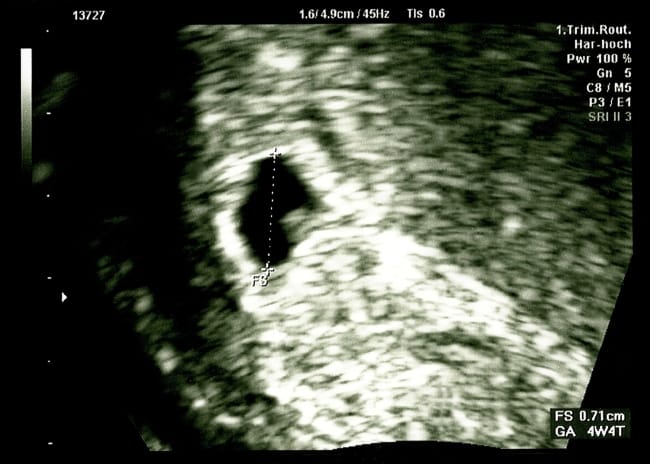

Pada usia kehamilan 4 minggu, ukuran kantung janin sangat kecil, yaitu sekitar 2–4 milimeter. Namun, Bunda nggak perlu khawatir, karena seiring bertambahnya usia kehamilan dan meningkatnya kadar hormon kehamilan, kantung janin akan terus berkembang kok.

Karena ukurannya yang masih sangat kecil, untuk melihat kantung janin 4 minggu, Bunda perlu menjalani pemeriksaan USG transvaginal, yaitu USG yang dilakukan melalui vagina. Pasalnya, USG lewat perut (transabdominal) terkadang kurang bisa mendeteksi adanya kantung janin 4 minggu.